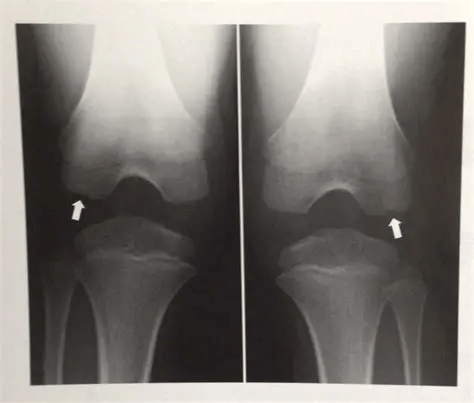

你可能很难想象,对一位老人而言,一次不经意的动作:走路绊了一下、从椅子上没坐稳滑下来,甚至仅仅是一个剧烈的咳嗽或喷嚏,都可能成为压垮身体的最后一根稻草。这在医学上被称为“脆性骨折”,即骨骼在几乎微不足道的能量冲击下,就发生了断裂。而“脆性”的背后,正是我们常说的骨质疏松。这种疾病无声无息,却能让原本坚实的骨骼变得脆弱不堪。

骨骼在轻微外力下即发生骨折,称为“脆性骨折”